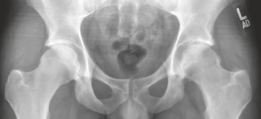

Standard anteroposterior (AP) pelvis and lateral hip radiographs are often the initial diagnostic step, but they may only show non-specific regional osteopenia or subtle cortical thickening in intra-articular cases.

High-resolution, thin-slice computed tomography (CT) with multiplanar reconstruction is the gold standard for defining the osseous anatomy. The CT scan accurately delineates the nidus as a well-circumscribed, radiolucent focus, often containing a central fleck of mineralization, surrounded by varying degrees of sclerosis. The surgeon must meticulously map the location of the nidus relative to reliable arthroscopic landmarks, such as the medial synovial fold, the zona orbicularis, and the articular margin of the femoral head.

Magnetic resonance imaging (MRI) is highly sensitive for detecting the profound bone marrow edema and adjacent soft tissue inflammation characteristic of osteoid osteomas. While MRI may obscure the nidus itself due to the overwhelming edema signal, it is invaluable for assessing the extent of reactive synovitis, evaluating the integrity of the articular cartilage, and identifying concurrent labral pathology.